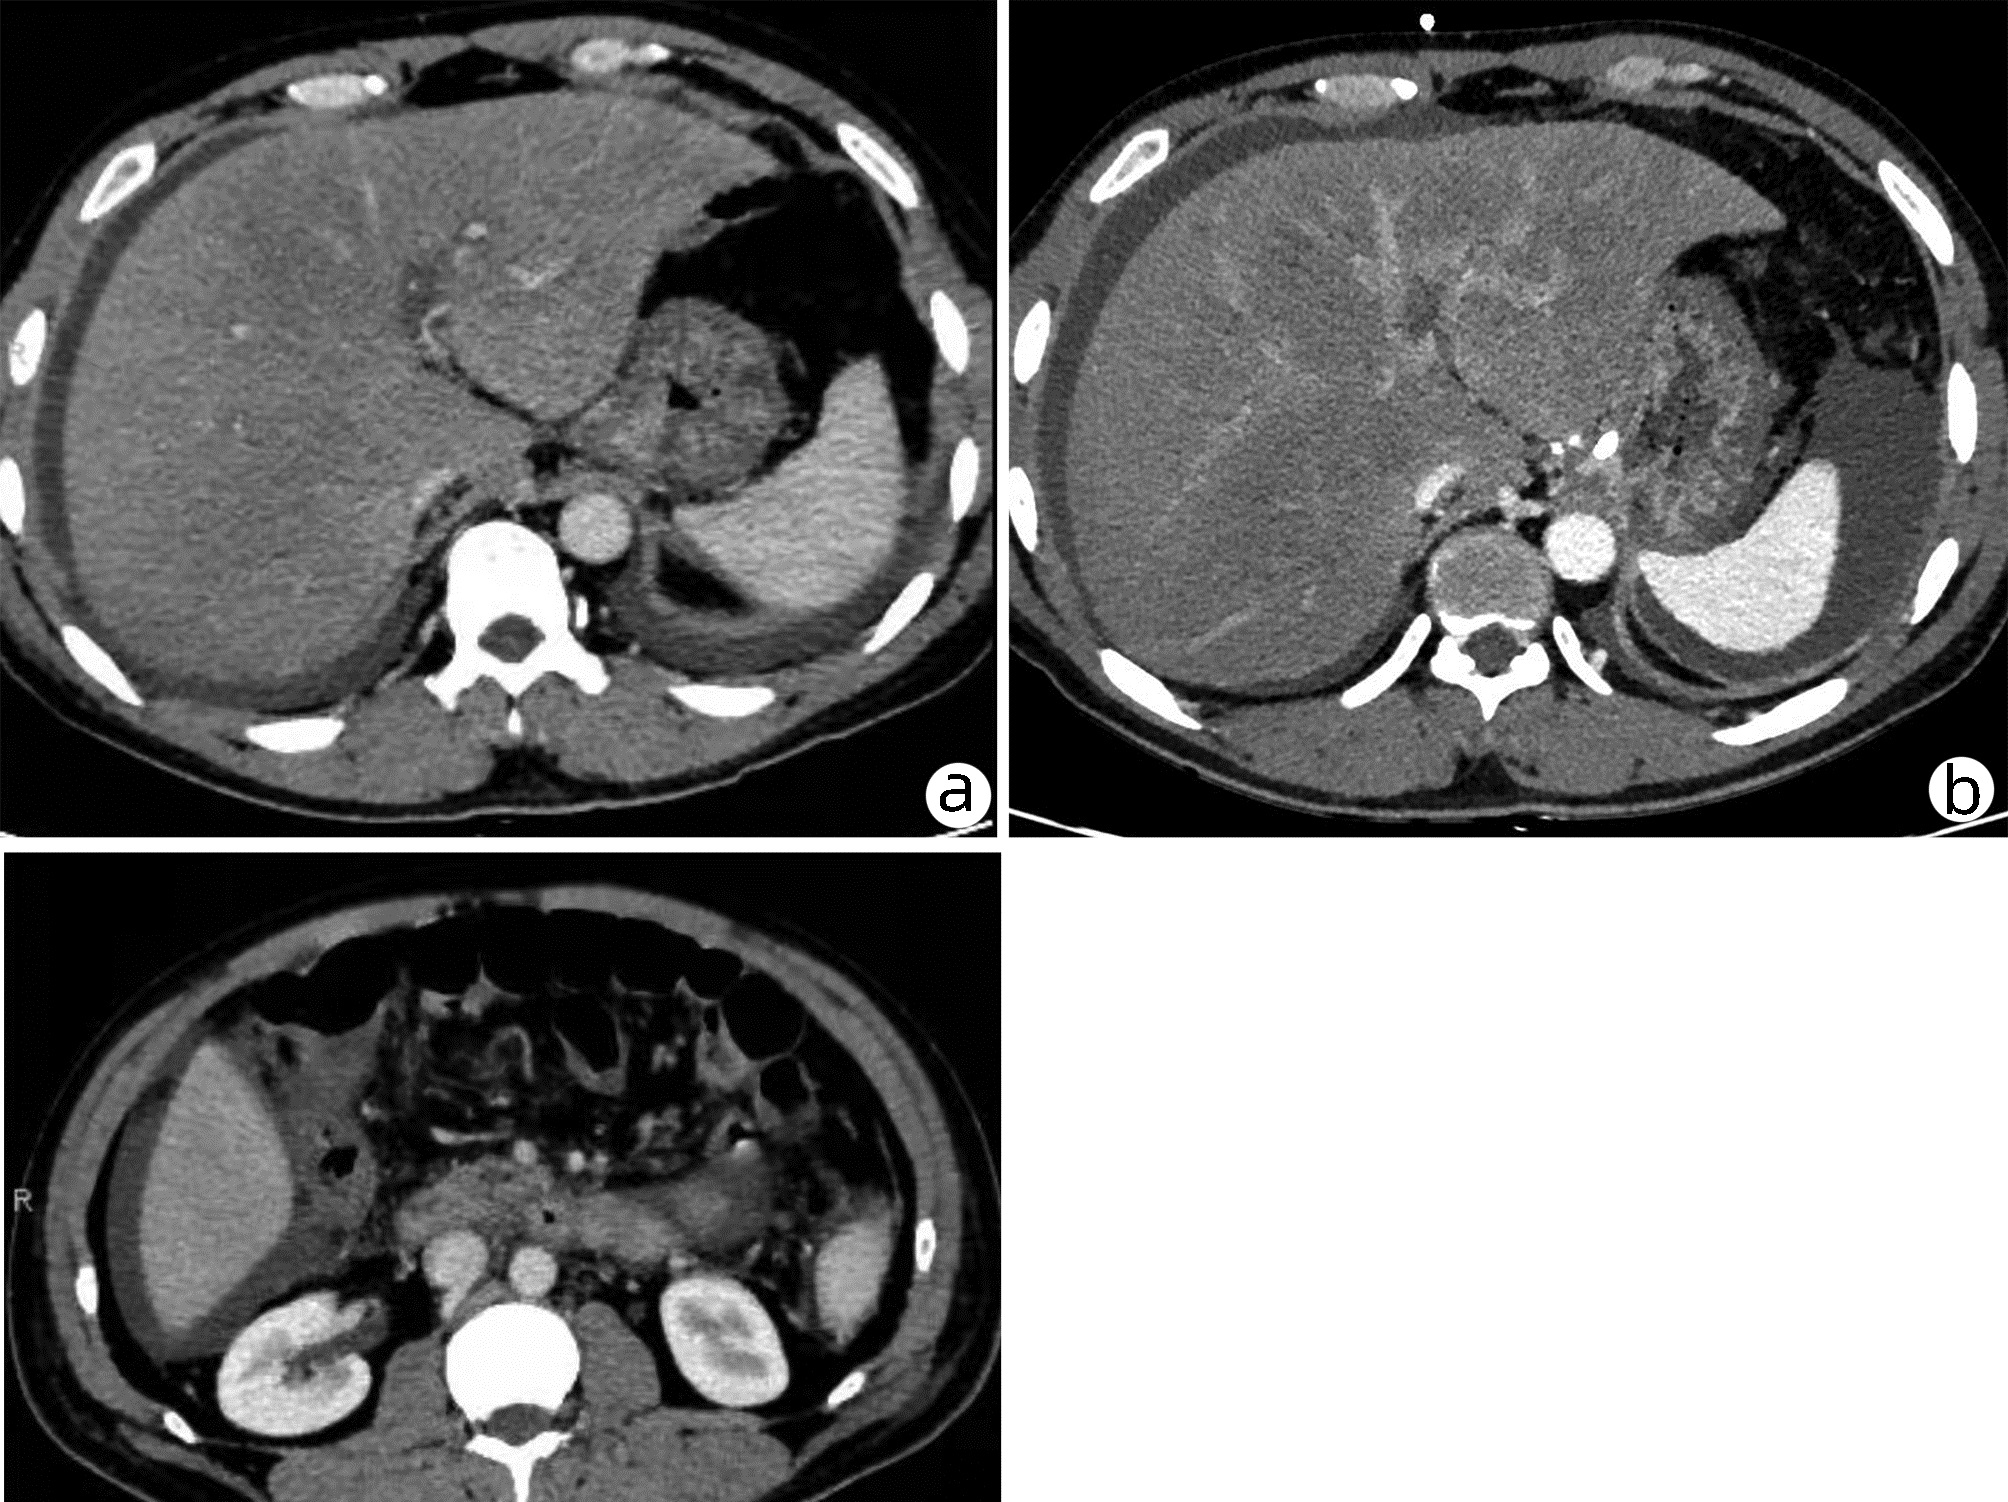

可切除胰腺癌术前评分分级体系的建立与应用

王成方, 王之江, 王伟林

2022, 38(10): 2325-2333. DOI: 10.3969/j.issn.1001-5256.2022.10.023

摘要(1020) HTML (588) PDF (2058KB)(81)

摘要:

目的  探讨分析可切除胰腺癌早期复发的危险因素及评分分级体系的建立与应用。  方法  采用回顾性病例对照研究方法,纳入浙江大学医学院附属第二医院肝胆胰外科2015年3月—2021年6月行根治性切除手术的可切除胰腺癌患者303例,其中283例直接手术患者分为早期复发组(术后6个月内)(n=95)和非早期复发组(n=188);术前行新辅助治疗患者20例为新辅助治疗组。观察指标包括患者的一般资料及术前影像资料;患者术前实验室检验资料,血常规、血生化及衍生指标,肿瘤标志物及凝血指标;随访获得无复发生存情况。正态分布的计量资料两组间比较采用t检验;非正态分布的计量资料两组间比较采用Mann-Whitney U检验。计数资料两组间比较采用χ2检验。通过受试者工作特征曲线确定各指标的最佳临界值。采用多因素Logistic回归分析胰腺癌患者早期复发的危险因素。绘制Kaplan-Meier曲线并采用Log-rank检验比较各组患者的无复发生存期。  结果  单因素分析结果显示,与非早期复发组相比,早期复发组患者BMI、甘油三酯较低,CA19-9、CA242、CA125、血浆纤维蛋白原较高(P值均<0.05)。多因素Logistic回归分析结果显示,BMI(OR=1.150,95%CI:1.038~1.273,P=0.007)、血浆纤维蛋白原(OR=2.513,95%CI:1.355~4.663,P=0.003)和CA242(OR=2.482,95%CI:1.067~5.774,P=0.035)是可切除胰腺癌患者早期复发的独立危险因素。将BMI、CA242、血浆纤维蛋白原3项指标纳入评分分级体系,临界值分别为23.00 kg/m2、30.00 U/mL和4.00 g/L。BMI<23.00 kg/m2计为1分,否则计为0分;CA242≥30.0 U/mL计为1分,否则0分;血浆纤维蛋白原≥4.00 g/L计为1分,否则0分,总分为0~3分。对早期复发与非早期复发患者进行评分,结果显示早期复发组评分更高[2(0~3)分vs 1(0~3)分,Z=-5.339,P<0.001]。Kaplan-Meier曲线分析结果显示,不同评分组别的患者无复发生存时间比较差异有统计学意义(χ2=28.116,P<0.001),分值越高预期无复发生存时间越短。将3分定义为高危组,0~2分定义为低危组。高危组早期复发率为84.6%,低危组早期复发率为31.2%。  结论  基于BMI、血浆纤维蛋白原和CA242这3项指标建立的评分系统能够在一定程度上预测患者术后复发情况。